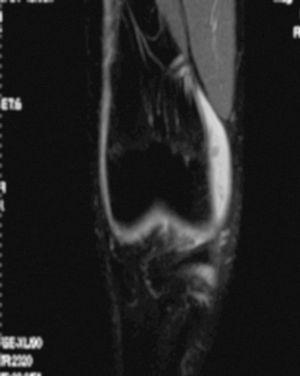

La RM muestra (figs. 1, 3 y 5):

Figura 3 RM. Imagen potenciada en T2 con supresión de grasa. Lesión condral amplia en rótula, faceta externa y cresta condral.

• Lesión condral amplia en faceta externa y cresta de rótula, de grosor parcial.

Se practica artroscopia, en la que se observan (figs. 2, 4, 6-8):

• Lesión condral anfractuosa extensa, con fragmentos inestables en cresta de la rótula y en faceta externa, de grado III.